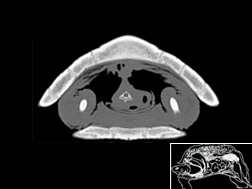

Atlas cérébral du chat IRMT2

IRM T2

31 coupes

Atlas cérébral du chat IRMT1

IRM T1

>> 31 coupes

Atlas cérébral du chat SCTM

Scanner tissu mou

>> 18 coupes

Atlas cérébral du chat SCTO

Scanner tissu osseux

>> 18 coupes